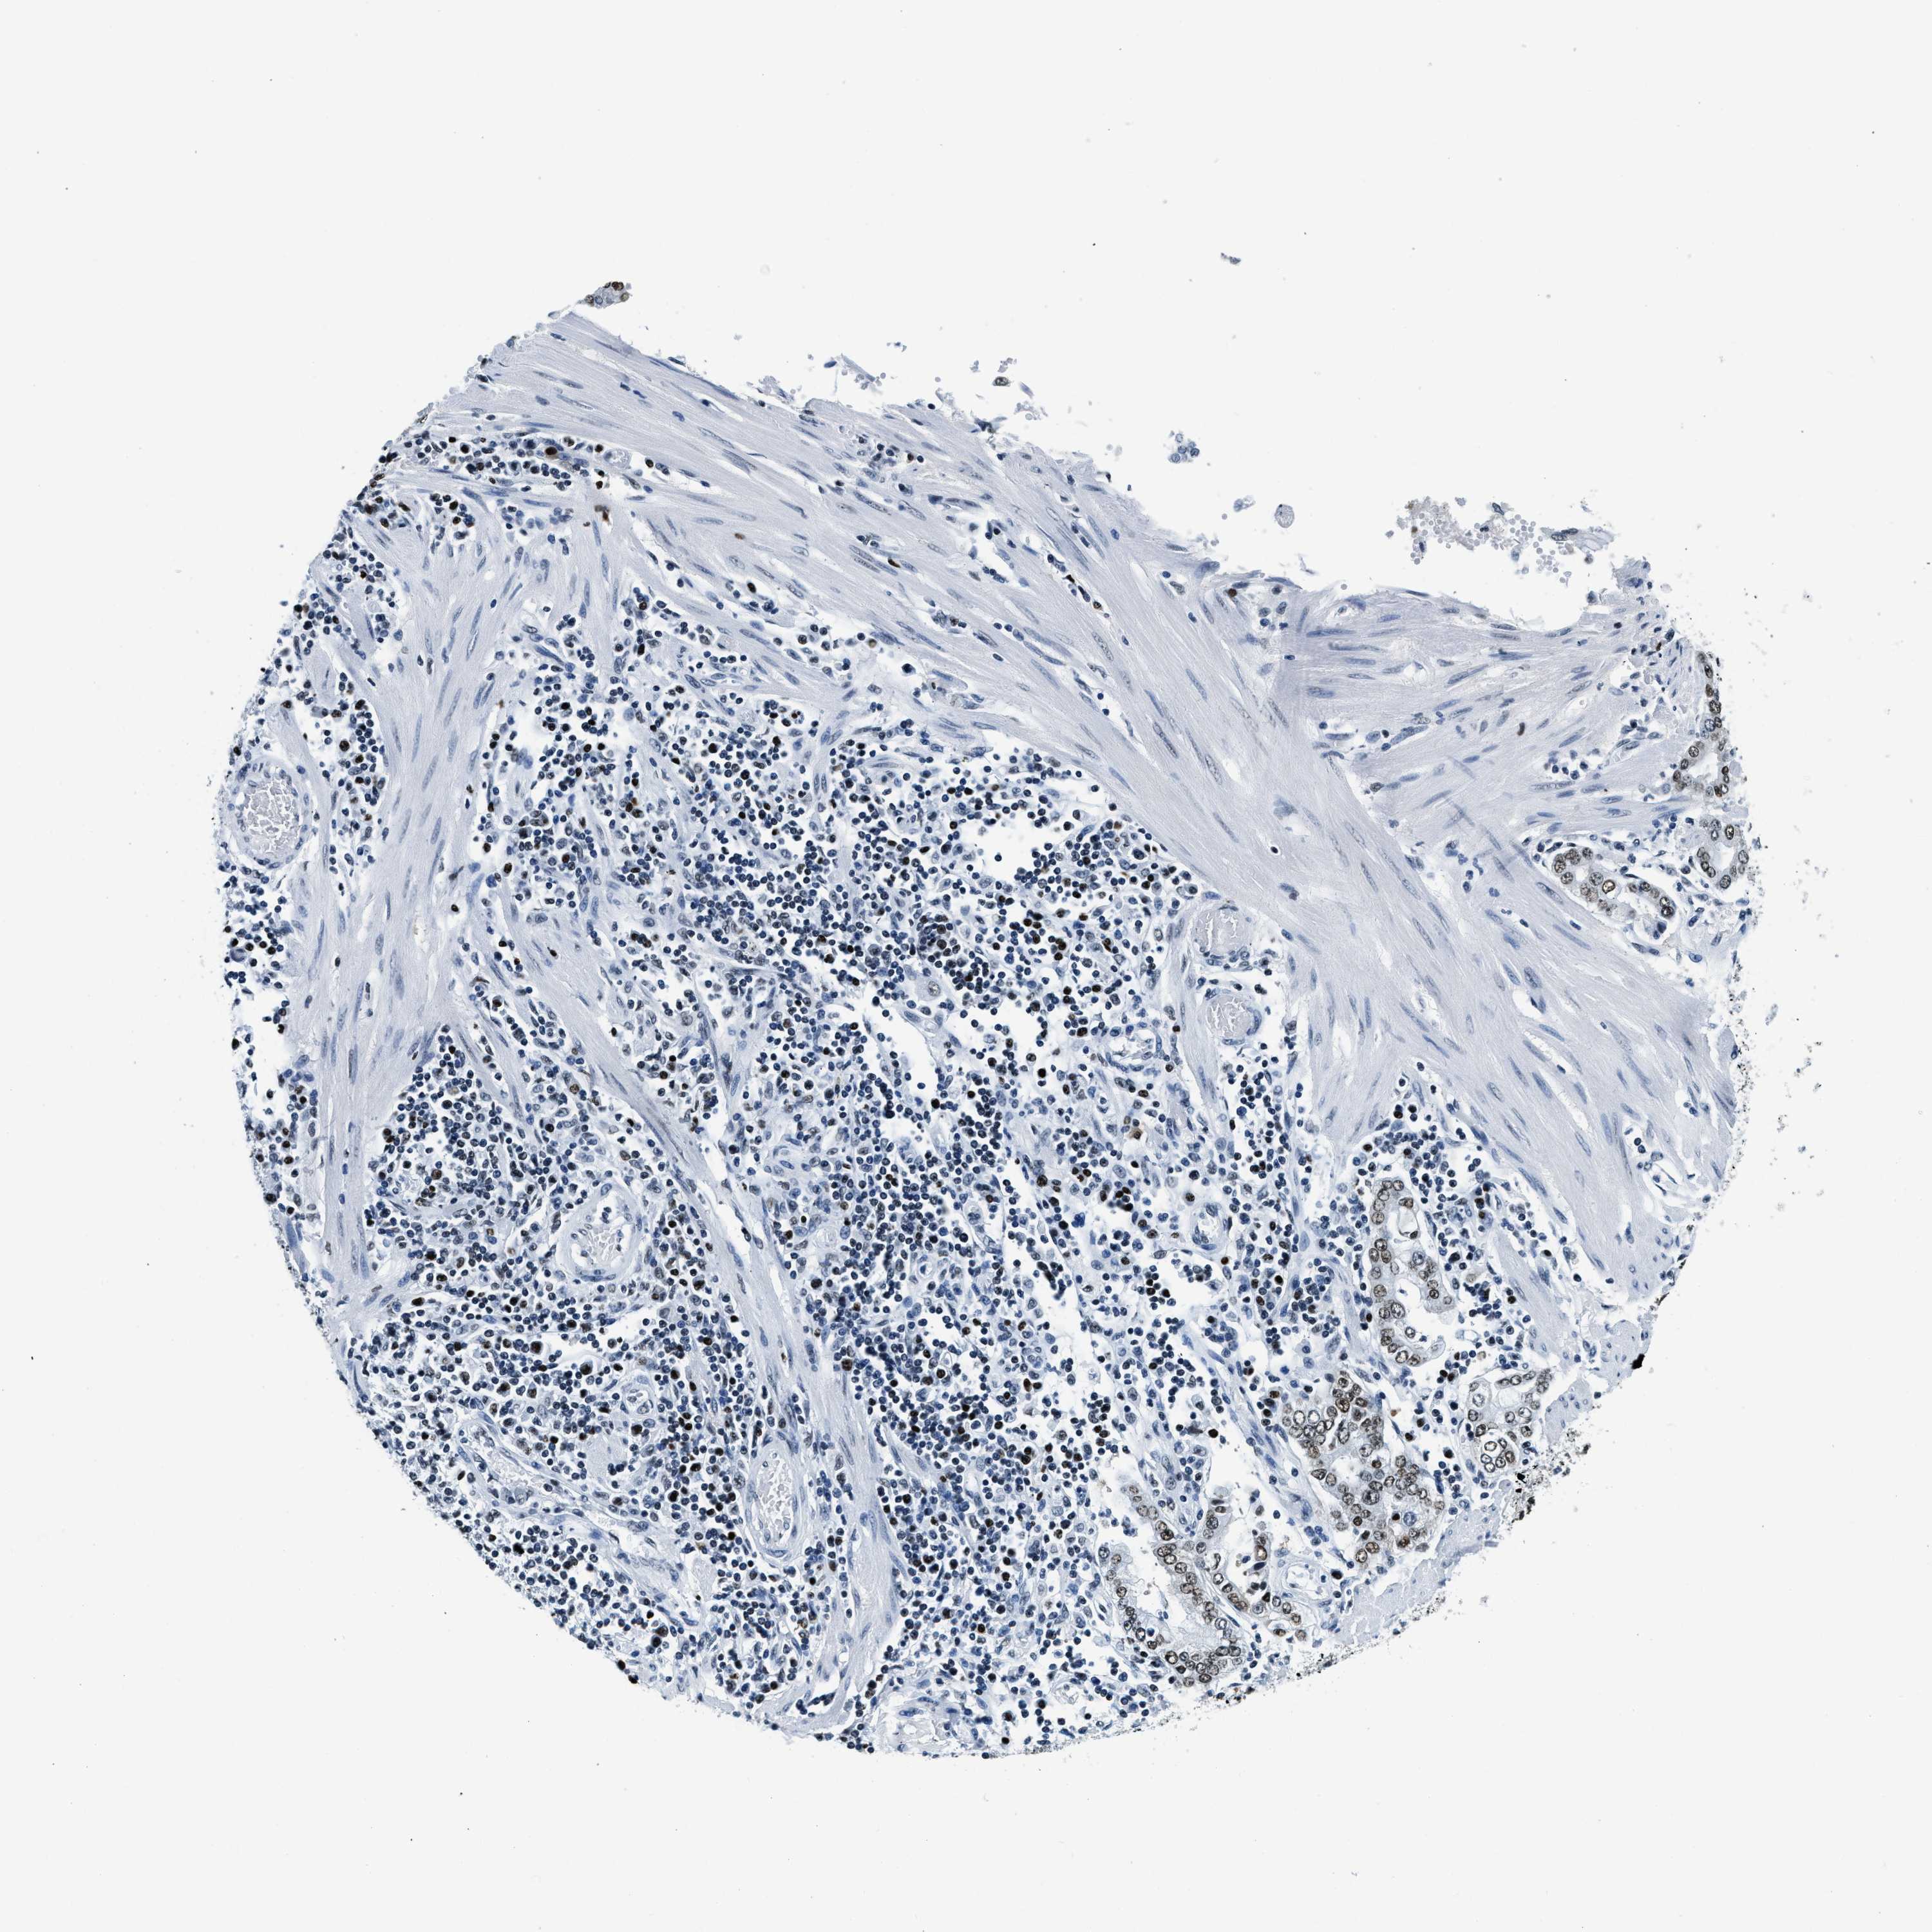

STOMACH CANCER - Protein expressioni

A mouse-over function shows sample information and annotation data. Click on an image to view it in a full screen mode. Samples can be filtered based on level of antibody staining by selecting one or several of the following categories: high, medium, low and not detected. The assay and annotation is described here.

Antibody stainingi

Antibody staining in the annotated cell types in the current human tissue is reported as not detected, low, medium, or high, based on conventional immunohistochemistry profiling in selected tissues. This score is based on the combination of the staining intensity and fraction of stained cells.

Each image is clickable and will lead to virtual microscopy that enables deeper exploration of all samples and also displays staining intensity scores, fraction scores and subcellular localization as well as patient and tissue information for each sample.

Antibody HPA019039

Antibody CAB009058

Staining

High

Medium

Low

Not detected

Intensity

Strong

Moderate

Weak

Negative

Quantity

>75%

75%-25%

<25%

None

Location

Nuclear

Cytoplasmic/membranous

Cytoplasmic/membranous,nuclear

Adenocarcinoma, NOS